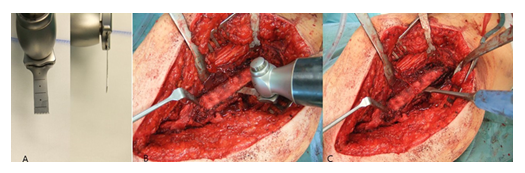

The technique is described based on the intraoperatively taken photos of patient no. 16.

All patients were placed in lateral position (Figure 1A). Under fluoroscopic control, the length of the skin incision was determined (Figure 1B). After transection of the skin and subcutis, the fascia lata was split in line with the skin incision. A standard transgluteal approach according to Bauer was utilized (Figure 1C).

After capsulotomy and stem dislocation, the leg was placed into the four position. The cone region was debrided, and the cement around the proximal part of the stem could be removed by thin osteotomes. A universal extractor was routinely used for stem removal, which usually occurred easily in the cemented cases (Figure 2A).

Figure 2: A: Removal of the stem with a universal extractor.; B: Identification of the proximal dorsal border of the M. vastus lateralis at its insertion, immediately anterior to the tendon of the M. gluteus maximus,; C: Medial retraction of the M. vastus lateralis by Hohmann retractors.; D: Determination of the length of the femur osteotomy.

Following stem removal, the leg was placed back to the original position. Then, the proximal dorsal border of the M. vastus lateralis was identified at its origin on the Tuberculum innominatum, immediately anterior to the tendon of the M. gluteus maximus (Figure 2B). Using a diathermy knife, the dorsal border of the M. vastus lateralis was detached from the lateral intermuscular septum until distally. Perforated vessels were identified and ligated. Then, the musculature was retracted anteriorly with a rasparatory, and Hohmann elevators were inserted for medial retraction (Figure 2C). Under fluoroscopic control, the length of the femur osteotomy was determined. The femur osteotomy should end immediately below the distal part of the cement or the stem tip (Figure 2D).

For the oscillating osteotomy, a blade sized 35x10x0.8mm (Fa. SMS medipool AG, Friedrichstal, Germany) was used (Figure 3A). The dorsal border of the osteotomy was the Linea aspera. For prevention of an intraoperative fracture, the width of the osteotomy should not exceed one third of the femoral circumference. Special attention should be paid that the osteotomy occurs convergent to the femur level (Figure 3B), which allows for an excellent re-adaptation of the bone flap later. After completion of the osteotomy, the femur could be carefully opened with a thin osteotome (Figure 3C).